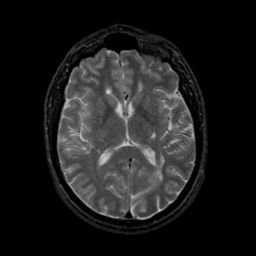

MR Study #9, April 14, 1991 -- Slice #27